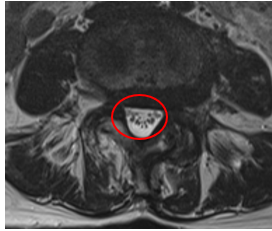

治療後

腰痛と、左下肢の痛み・痺れの根本原因であるL4/5の狭窄を取り除く手術「PEL」を施し、神経の圧迫を取り除きました。またこの手術時には、神経細胞の修復作用効果を期待して、濃縮血小板由来の成長因子を患部に注入する再生医療「PRP療法」を行いました。

┃治療後の経過

手術の翌日には痛みと痺れが軽減。椅子から立ち上がるときに痛みを感じなくなるほど回復しました。術後2か月経過時には主症状に挙げていた痛みは手術前と比べて10から1に、痺れは10から0になりました。